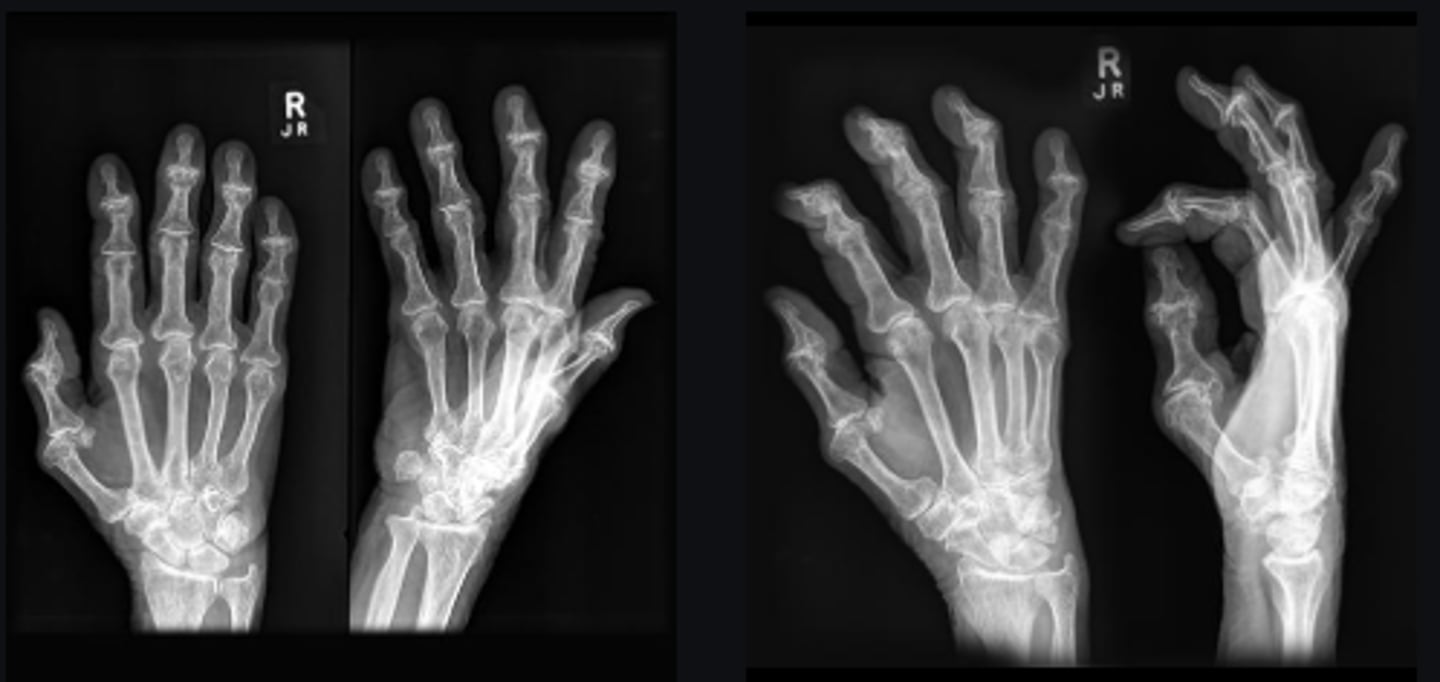

- PIPs and DIPs involved

- Thick/swollen hand

- Gull-wing deformity

- Osteophytes

Describe findings

Erosive osteoarthritis

Diagnosis?

Middle-aged females

What patient population generally gets this disease?